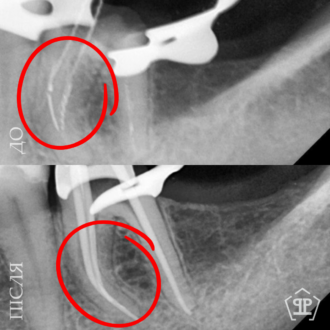

Пациент нуждался в повторном лечении корневых каналов из-за осложнений предварительного лечения. Выполнено извлечение анкерного штифта, перелечивание корневых каналов, очищение и пломбирование с учетом анатомических особенностей зуба.

Во время диагностики обнаружен отлом фрагмента инструмента в корневом канале. Выполнено его безопасное извлечение, повторное перелечивание каналов, очистку и герметичное пломбирование.

Перелечивание с удалением двух переломанных инструментов. Пациент обратился с осложнением предварительного эндодонтического лечения. В каналах были обнаружены два переломанных инструмента. Выполнены их удаление и пломбирование каналов с соблюдением современных эндодонтических протоколов.